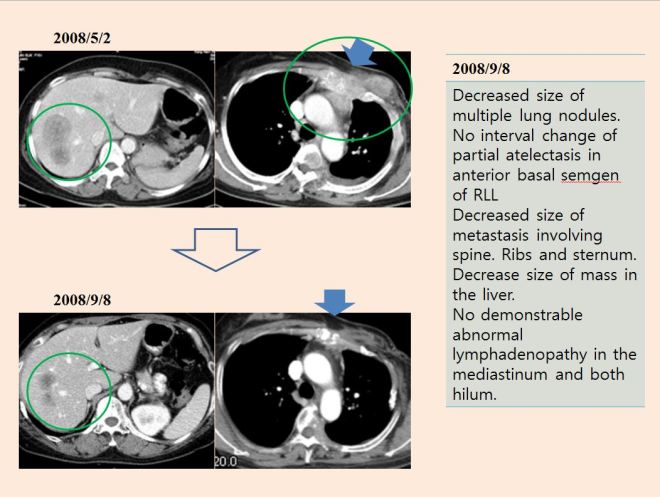

위에서 보듯이 2013년 11월 사진을 보면 전폐에 솜뭉치같이 뭉글 뭉글하게 보이는 하얀 원형의 점들이 모두 암이 퍼진모습이다.